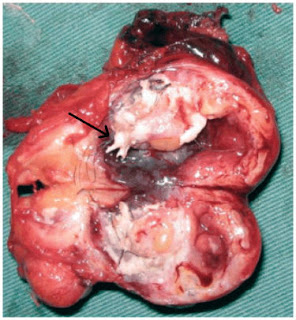

The upper image shows the PNEC’s in your respiratory tract (NE). They can be alone or be grouped into neuro- endocrine bodies (NEBs). A 2008 study, and several before it, has correlated a hyperplasia and hypertrophy of PNECs with Sudden Infant Death Syndrome. Too many and your respiratory control may get thrown out of whack; it may just stop working. It might be good to monitor the PNEC system in youngsters to try and predict susceptibility to SIDS. |

They have several functions, including regulating the development of the respiratory system in the fetus. They also regulate the function of the respiratory cells by sensing oxygen levels, controlling the muscular tone of the bronchi, regulating pulmonary blood flow and modulating immune responses. The origin and function of PNEC’s is reviewed in a 2012 paper, which also highlights a problem with them – when PNEC’s go bad, they cause a deadly small cell cancer.